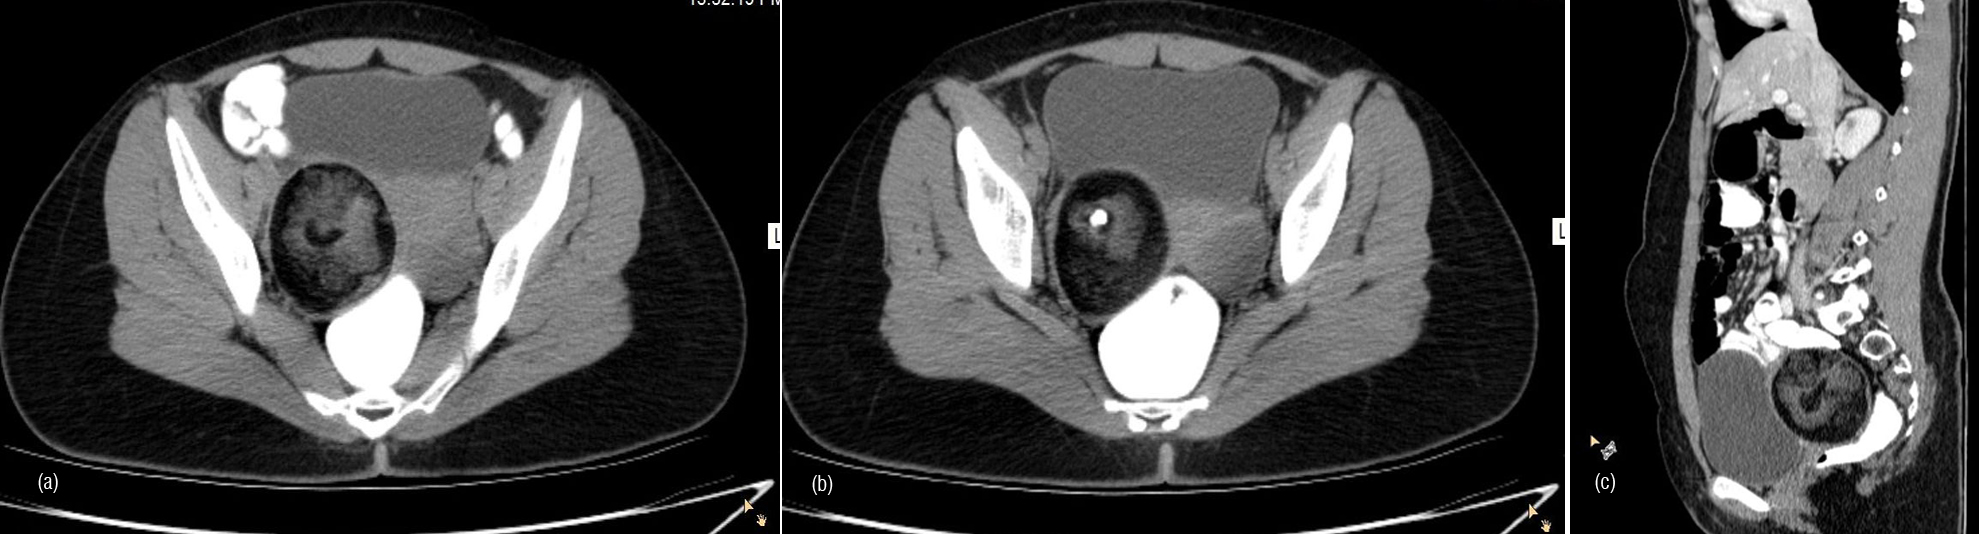

Malignant sex cord tumour and granulosa cell tumour are two types juvenile and adult type. Juvenile present before puberty and present with pseudo puberty. Adult type constitute 90% presenting with abnormal uterine bleeding. Granulosa cell tumour has tendency for hemoperitoneum. Size is variable. Morphology is variable may be cystic to complexly solid. They are associated with endometrial abnormality (Figure 16abc). Sertoli-Leydigcell tumour occur in younger age and tends to be unilateral. Size is variable may appear as solid/ solid with peripheral cyst/ cystic lesion with solid mural component or completely cystic. Well defined enhancing solid tumour with variable intra tumoural cystic component (Figure 17).

Figure 16a,b,c: Granulosa cell tumour.